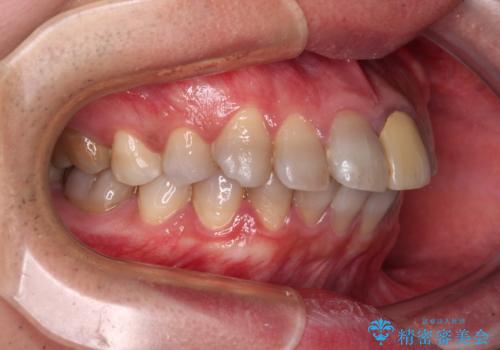

- 飛び出した前歯を気にして来院された患者様です。

口元を引っ込めるために上下左右の第一小臼歯4本を抜歯することとしました。

速やかに治療を進めたいとのことで、表側のワイヤー装置で矯正治療を行うこととしました。

特徴的な歯の色が気になっているとのことで、今後セラミッククラウンによる審美歯科治療を検討されているとのことで、矯正治療の後戻りが落ち着いたタイミングで治療を進めていく予定です。